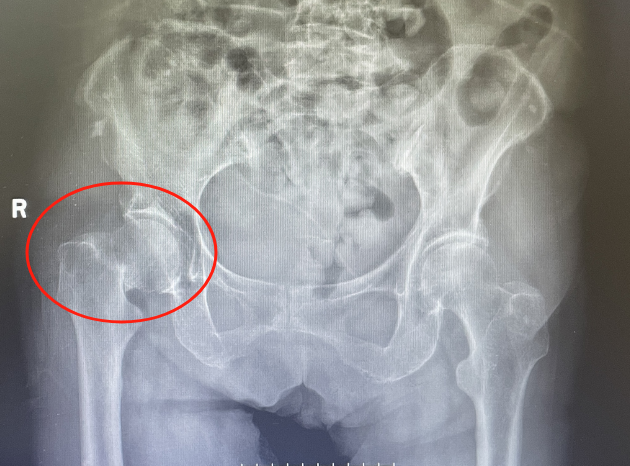

入院后检查发现老人右侧股骨颈骨折,更加麻烦的是张奶奶有高血压病、冠心病、脑梗塞等病史20余年。高龄、基础疾病多,手术风险高。但骨折后保守治疗,需要长期卧床,疼痛难忍,吃喝拉撒都要在床上进行,并发症多,生活质量下降。“手术?还是不手术?”张奶奶的家属可发了愁。“最好的方法还是控制内科疾病后,帮忙老人尽早手术治疗吧!”经过骨科副主任医师徐光辉耐心与家属沟通后,家属要求积极手术治疗。